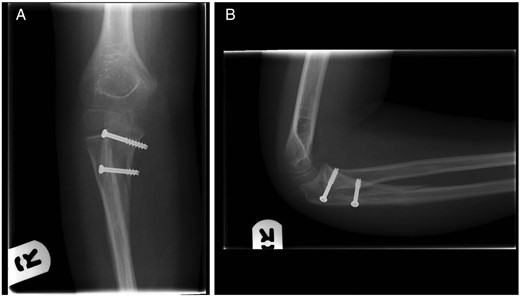

Five weeks following surgery, the fracture had clinically united and radiographs demonstrated maintenance of alignment and evidence of healing (Fig. 4). At a final review 4 months post-operatively he had a full range of motion of the elbow and forearm with no distal neurovascular deficit. The metalwork was not causing irritation and was therefore left in place.

(A) Anterior–posterior and (B) lateral radiographs of the right elbow. Images taken at 5 weeks post-reduction.